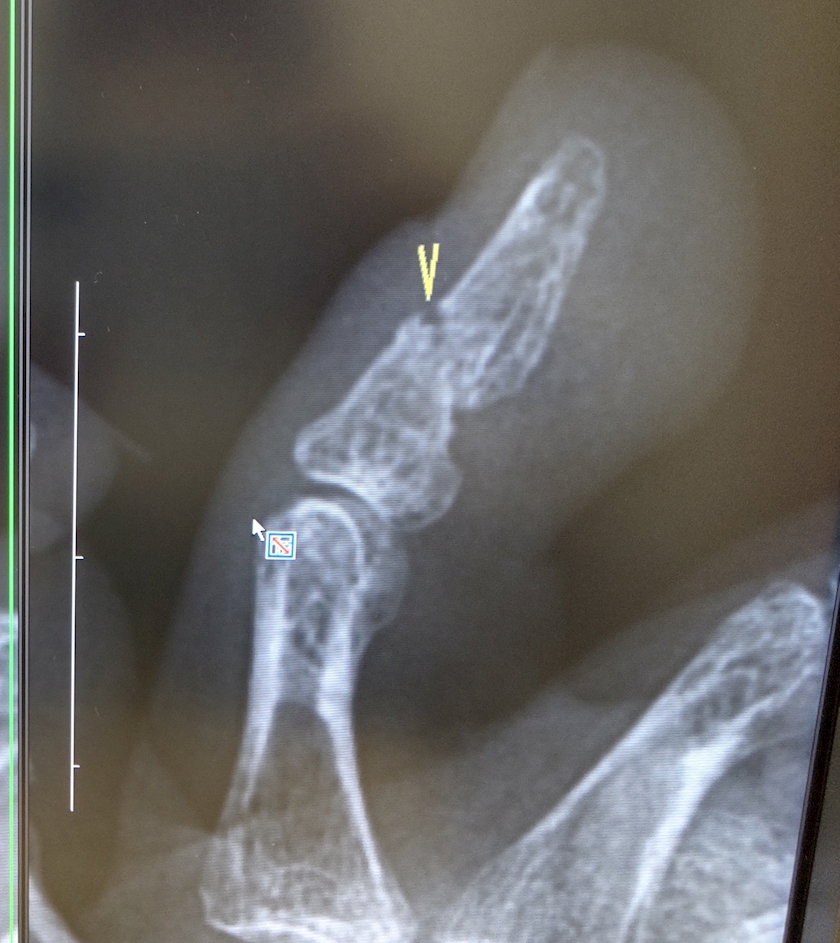

先日

最後の病院

…のつもりで挑んだレントゲン💀

画像入手

8割治ってきてるけど

まだつながってないそーで

(確かに。。

)もー少しの辛抱

次回は6月